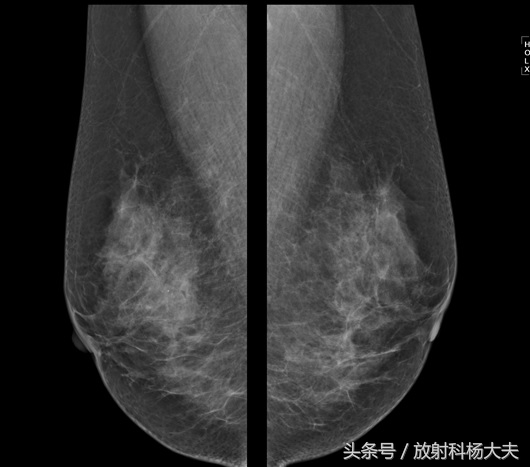

女性,腋窝下淋巴结肿大,几乎就等于是说同侧乳腺有癌了。可是,奇怪的是,这个女性双侧乳腺做了B超和钼靶,两个检查都是一个结论,没有发现乳腺癌,也就是BI-RADS都报了1类。

钼靶,BI-RADS 1类